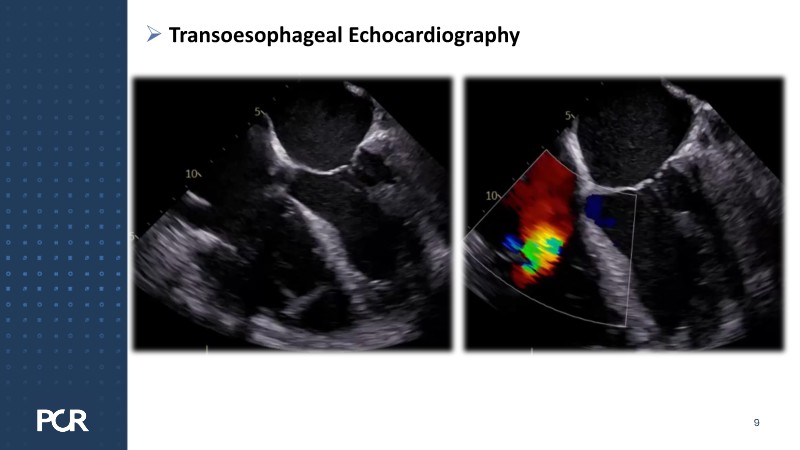

This session addresses emerging topics in structural heart disease by examining patient-centered solutions such as EVOQUE transcatheter tricuspid valve replacement (TTVR) and SAPIEN transcatheter heart valve-in-heart valve (THV-in-THV) procedures. It covers the latest data from Europe on redo TAVI, lifetime management strategies beginning with initial prosthesis planning, evolving patient selection for TTVR, and features an educational live case alongside expert panel discussions on procedure safety and efficacy.